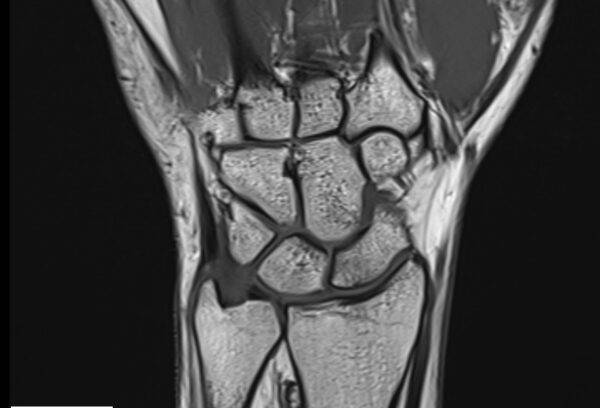

Und außerdem: Die Spulen, die das Bild machen, sind in der Röhre verbaut. Die müssen ja auch irgendwie nah ans Handgelenk rankommen, um scharfe Bilder zu liefern. Wäre ja doof, wenn man hinterher nur Matsch auf den Bildern hätte. Dann könnte man sich das ganze Spektakel ja gleich sparen!